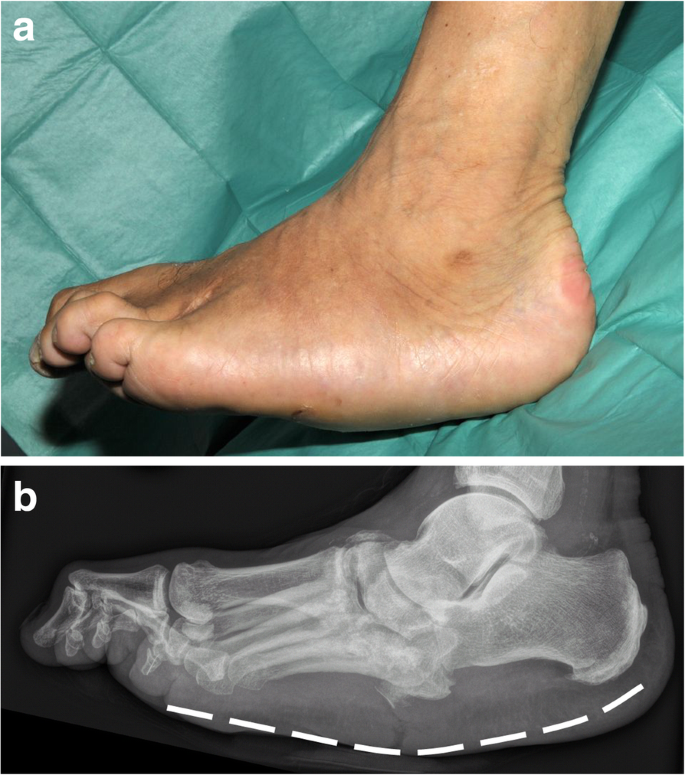

Charcot foot is a rare manifestation of peripheral neuropathy; it can also occur in individuals with diabetes mellitus due to loss of sensation in the peripheries. Unrecognized strain or any foot injury can go unnoticed; this leads to lack of foot care and consequent aberrant healing of the injury resulting in bone deformities or open wound leading to infection and eventual gangrene. The deformity of the bones can cause pressure sores. The bones, joints, and soft tissues of the foot are affected. If the bones of the midfoot are fractured, impaired healing may cause rock-bottom deformity. Since pain is absent in peripheral neuropathy, Charcot foot usually presents with redness and warmth. Xray plays a pivotal role in the diagnosis of Charcot foot. The management of Charcot foot is both surgical and non-surgical. The aims of treatment are to prevent further deformity, treat bone diseases, and to take the weight off the foot. Non-surgical management includes offloading (It refers to take the weight off the foot thereby reducing further injury. It also aids in decreasing inflammation.), protected-weight bearing, prescription orthopaedic footwear, and use of Charcot Restraint Orthotic Walker Surgical management is indicated in severe ankle and foot deformities that hinder the use of braces. Reference: https://my.clevelandclinic.org/health/diseases/15836-charcot-foot Image via: https://insightsimaging.springeropen.com/articles/10.1186/s13244-019-0768-9